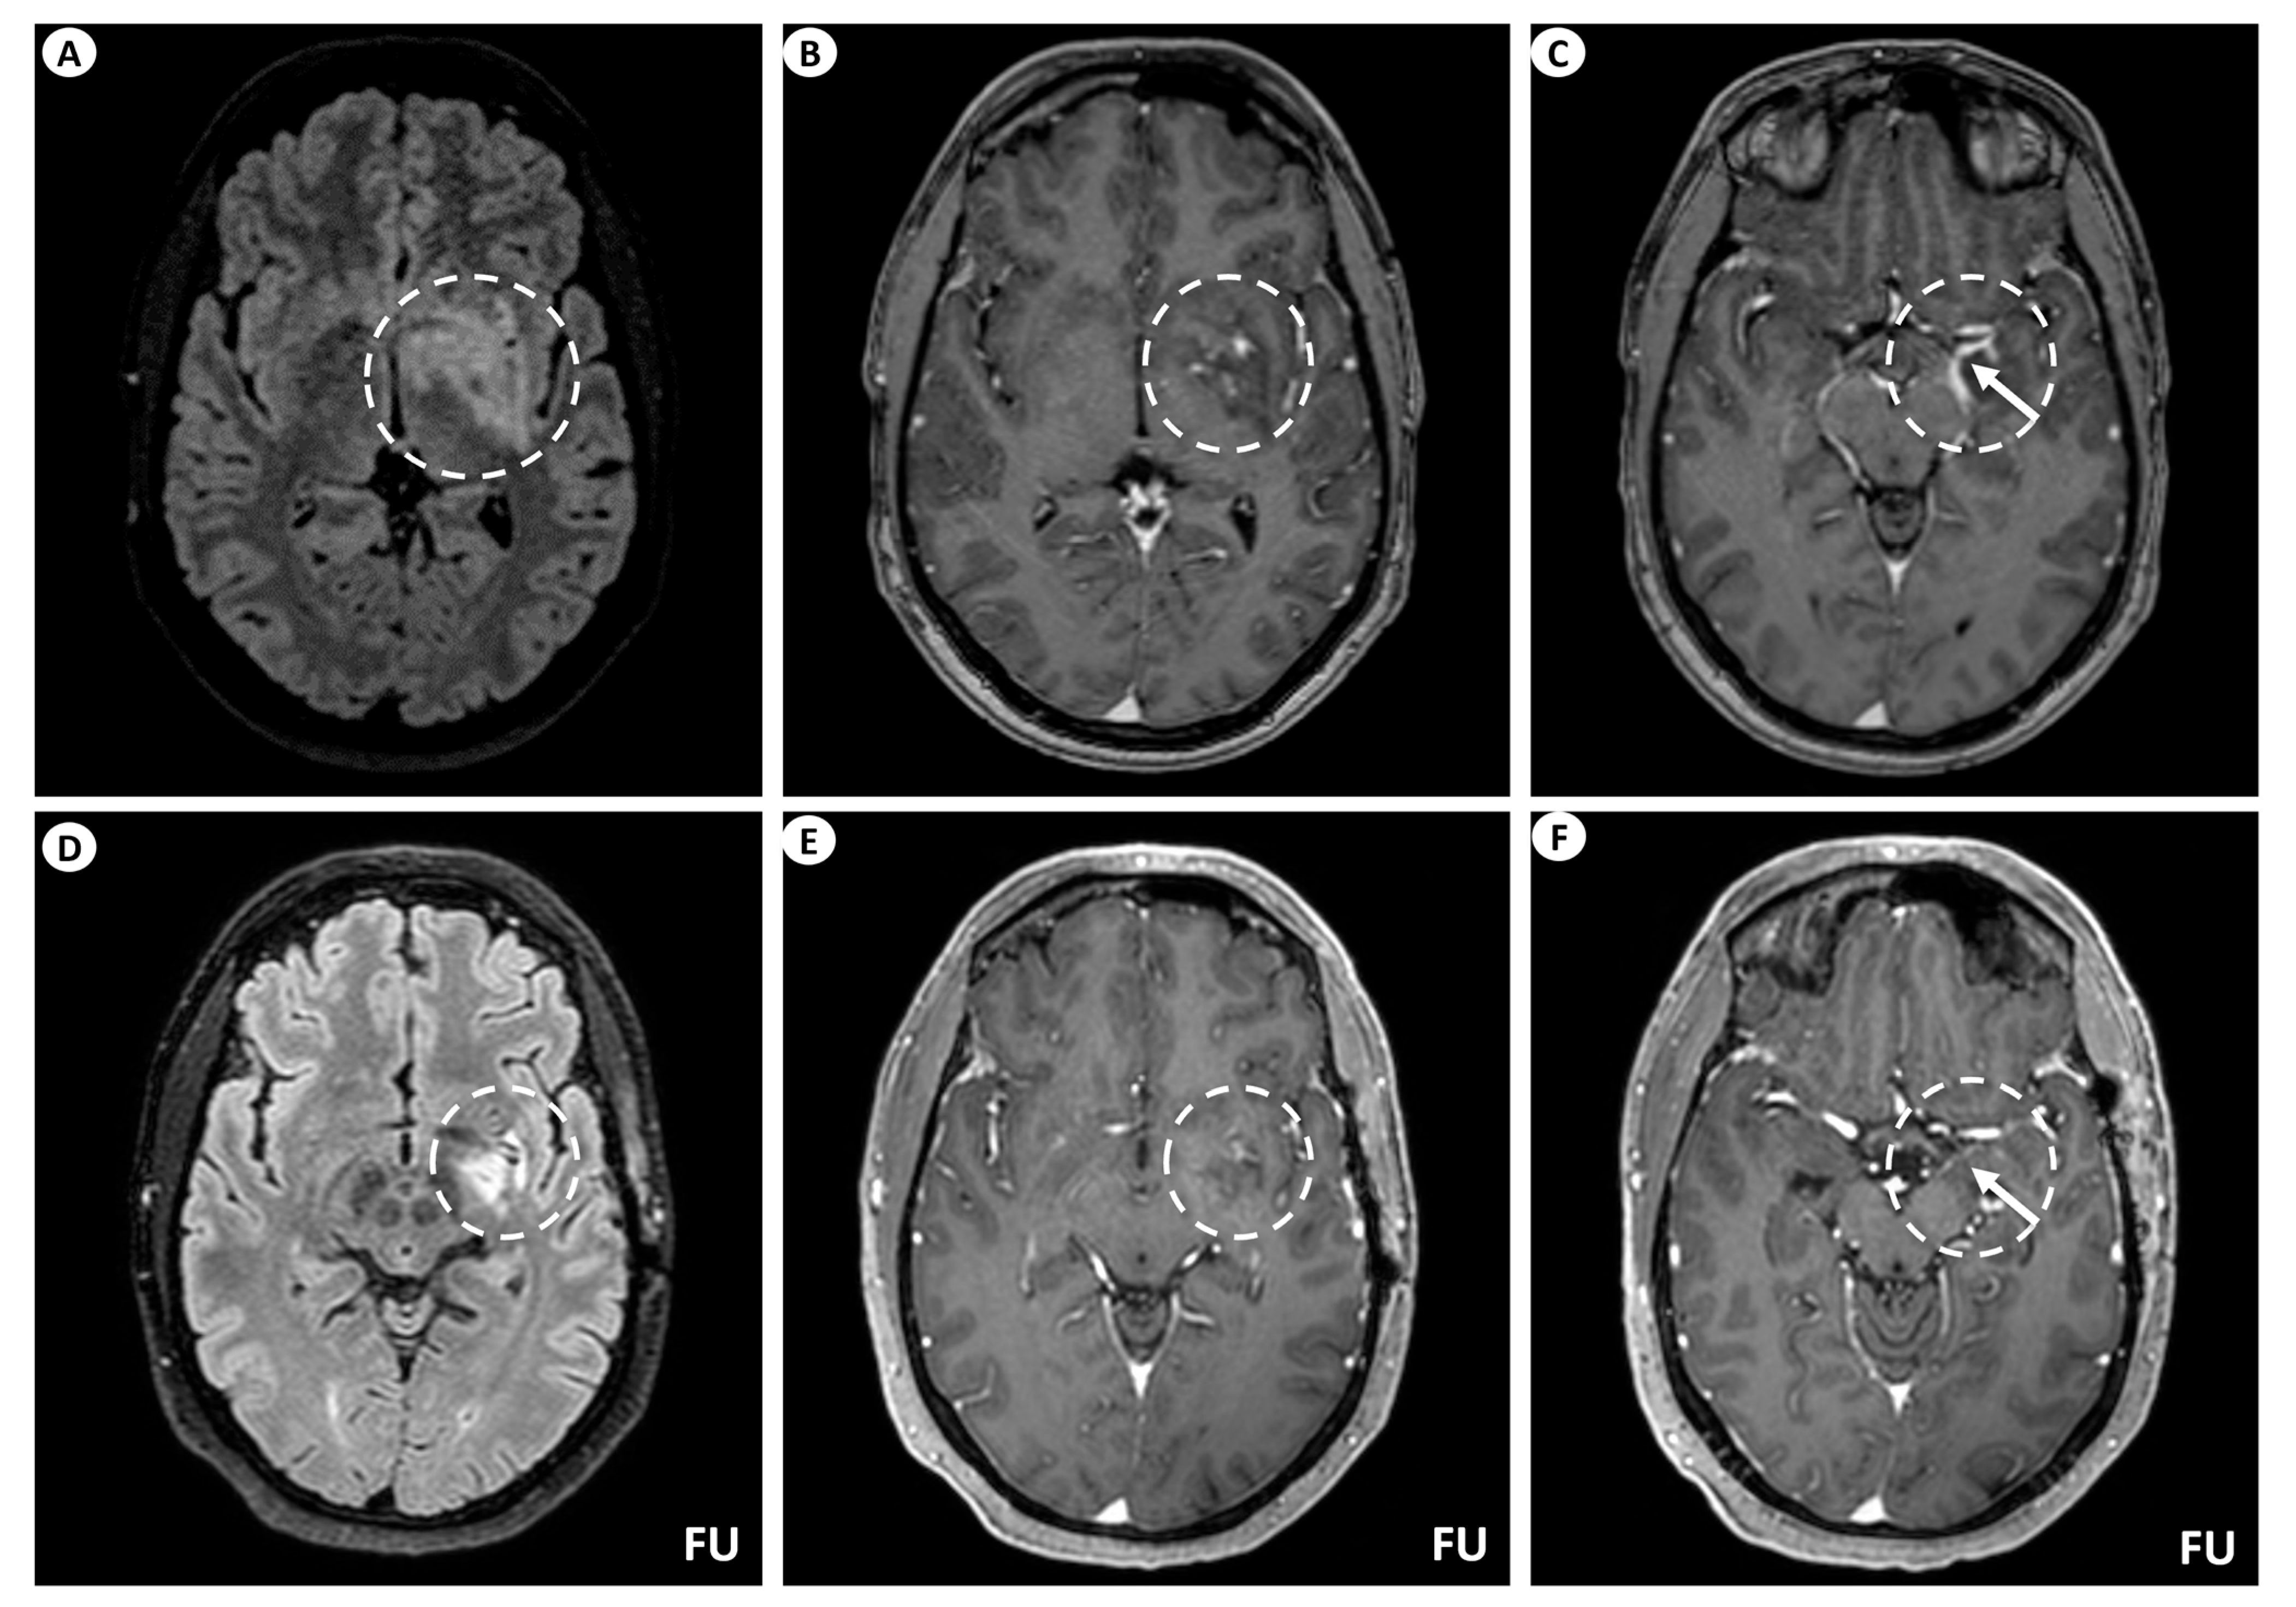

A 44-year-old man presented with persistent, left-sided, daily headache episodes of tightening quality and medium severity (visual analog scale score 6/10) over the past 15 days. No prior history of headaches was reported, and his past medical history was insignificant except for smoking (40 pack-years). Neurological examination was completely normal. Magnetic resonance imaging (MRI) of the brain revealed T2/fluid-attenuated inversion recovery (FLAIR) signal hyperintensity within the basal ganglia (putamen, globus pallidus), internal capsule, medial temporal lobe, hypothalamus, and midbrain on the left. Linear perivascular radial gadolinium enhancement was also observed, extending along the perivascular spaces in these areas, as well as leptomeningeal contrast enhancement along the surface of the uncus (Figure 1). The patient did not have a lumbar puncture but instead underwent a brain biopsy, which was inconclusive, and received a short course of oral steroids following the biopsy. He was subsequently lost to follow-up but was eventually readmitted for further investigations. At that time, he underwent a lumbar puncture, which showed no pleocytosis. Cerebrospinal fluid (CSF) protein, glucose levels, and IgG index were within normal ranges, while oligoclonal bands were negative. However, it is important to note that the lumbar puncture was performed 6 months after symptom onset and following steroid treatment. A second brain MRI showed significant improvement, with remission of the hyperintensities and of the contrast enhancement (Figure 1), while an MRI of the spinal cord did not reveal any signs of myelopathy or other abnormal findings. CSF and serum testing for GFAP antibodies returned positive, while antibody testing for autoimmune and paraneoplastic encephalitis, including surface and intracellular antibodies, was negative. The patient underwent computerized tomography (CT) of the chest and abdomen, which was normal, as well as a positron-emission tomography (PET) scan, which was negative for malignancy. Subsequently, he received a five-day course of intravenous (IV) steroids without tapering and has remained asymptomatic since then.

Figure 1.

Brain MRI of patient 1. (A) Axial T2-FLAIR (fluid-attenuated inversion recovery) images display signal hyperintensity centered within the basal ganglia (putamen, globus pallidus) and internal capsule on the left (dashed circle). (B) Axial T1-weighted images following intravenous gadolinium injection demonstrate punctate as well as linear contrast enhancement extending along the perivascular spaces (dashed circle), and (C) leptomeningeal contrast enhancement along the surface of the uncus (as indicated by the arrow within the dashed circle). Follow-up (FU) MRI examination in the same patient displays a noteworthy decrease in the extent of the signal hyperintensity within the left basal ganglia on axial T2-FLAIR images (dashed circle) (D). Similarly, axial T1-weighted images following intravenous gadolinium injection demonstrate partial subsidence of the perivascular contrast enhancement (dashed circle) (E), and complete resolution of the leptomeningeal enhancement (arrow within the dashed circle) (F).